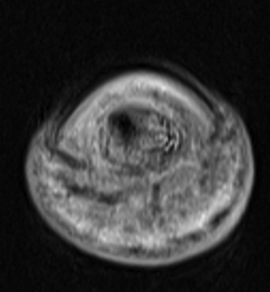

Figure 4 for case Osteoid osteoma ( RID4005 )

Figure 4